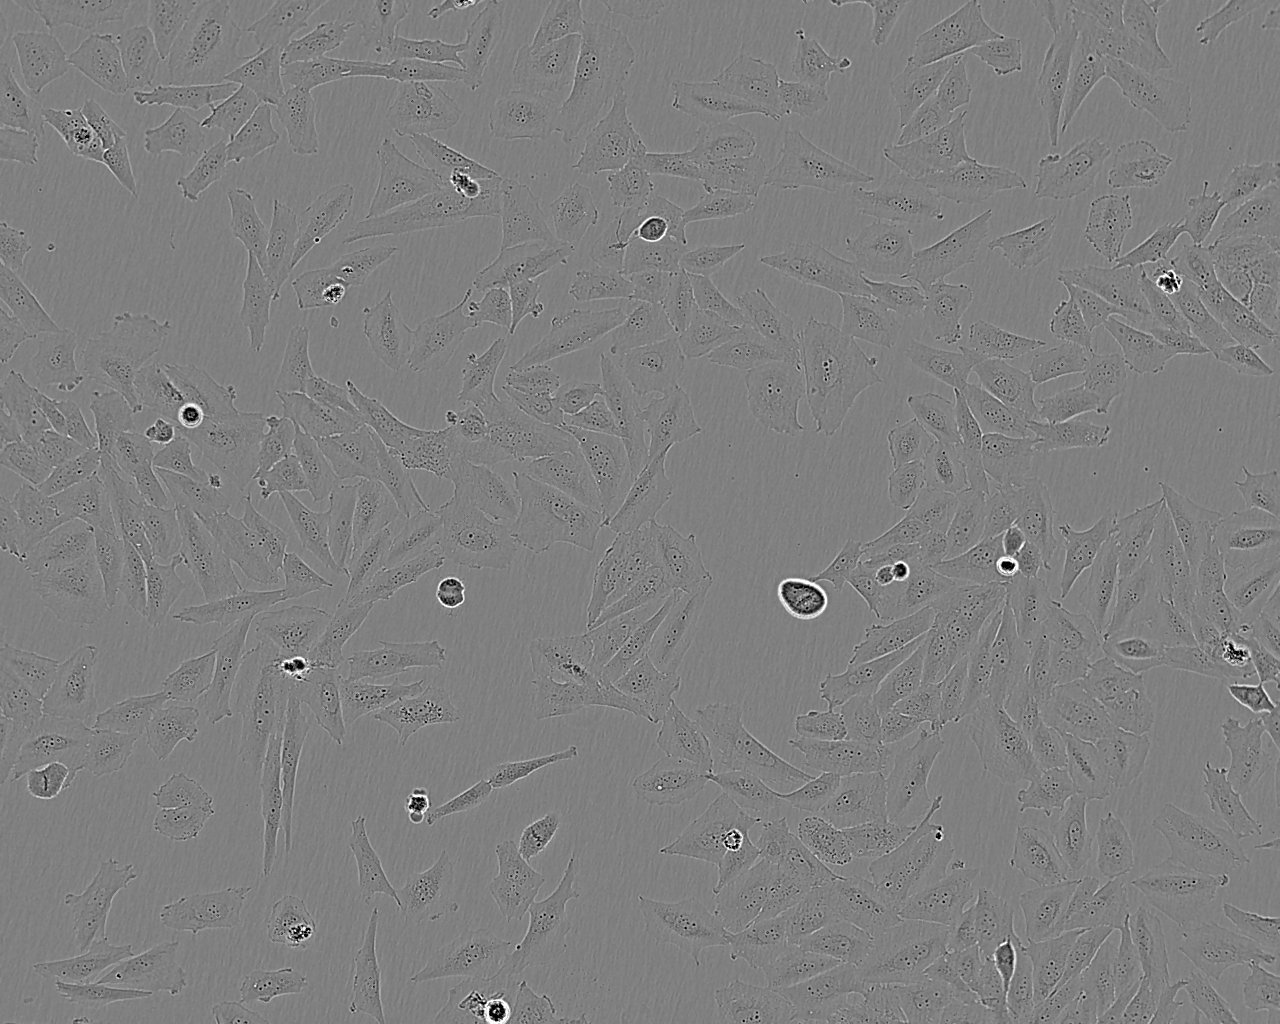

Cell Type

Epithelial-like

Split sub-confluent cultures (70-80%) 1:3 to 1:6 i.e. seeding at 1-4x10,000 cells/cm² using 0.05% trypsin or trypsin/EDTA; 5% CO₂; 37°C.

Growth Mode

Adherent